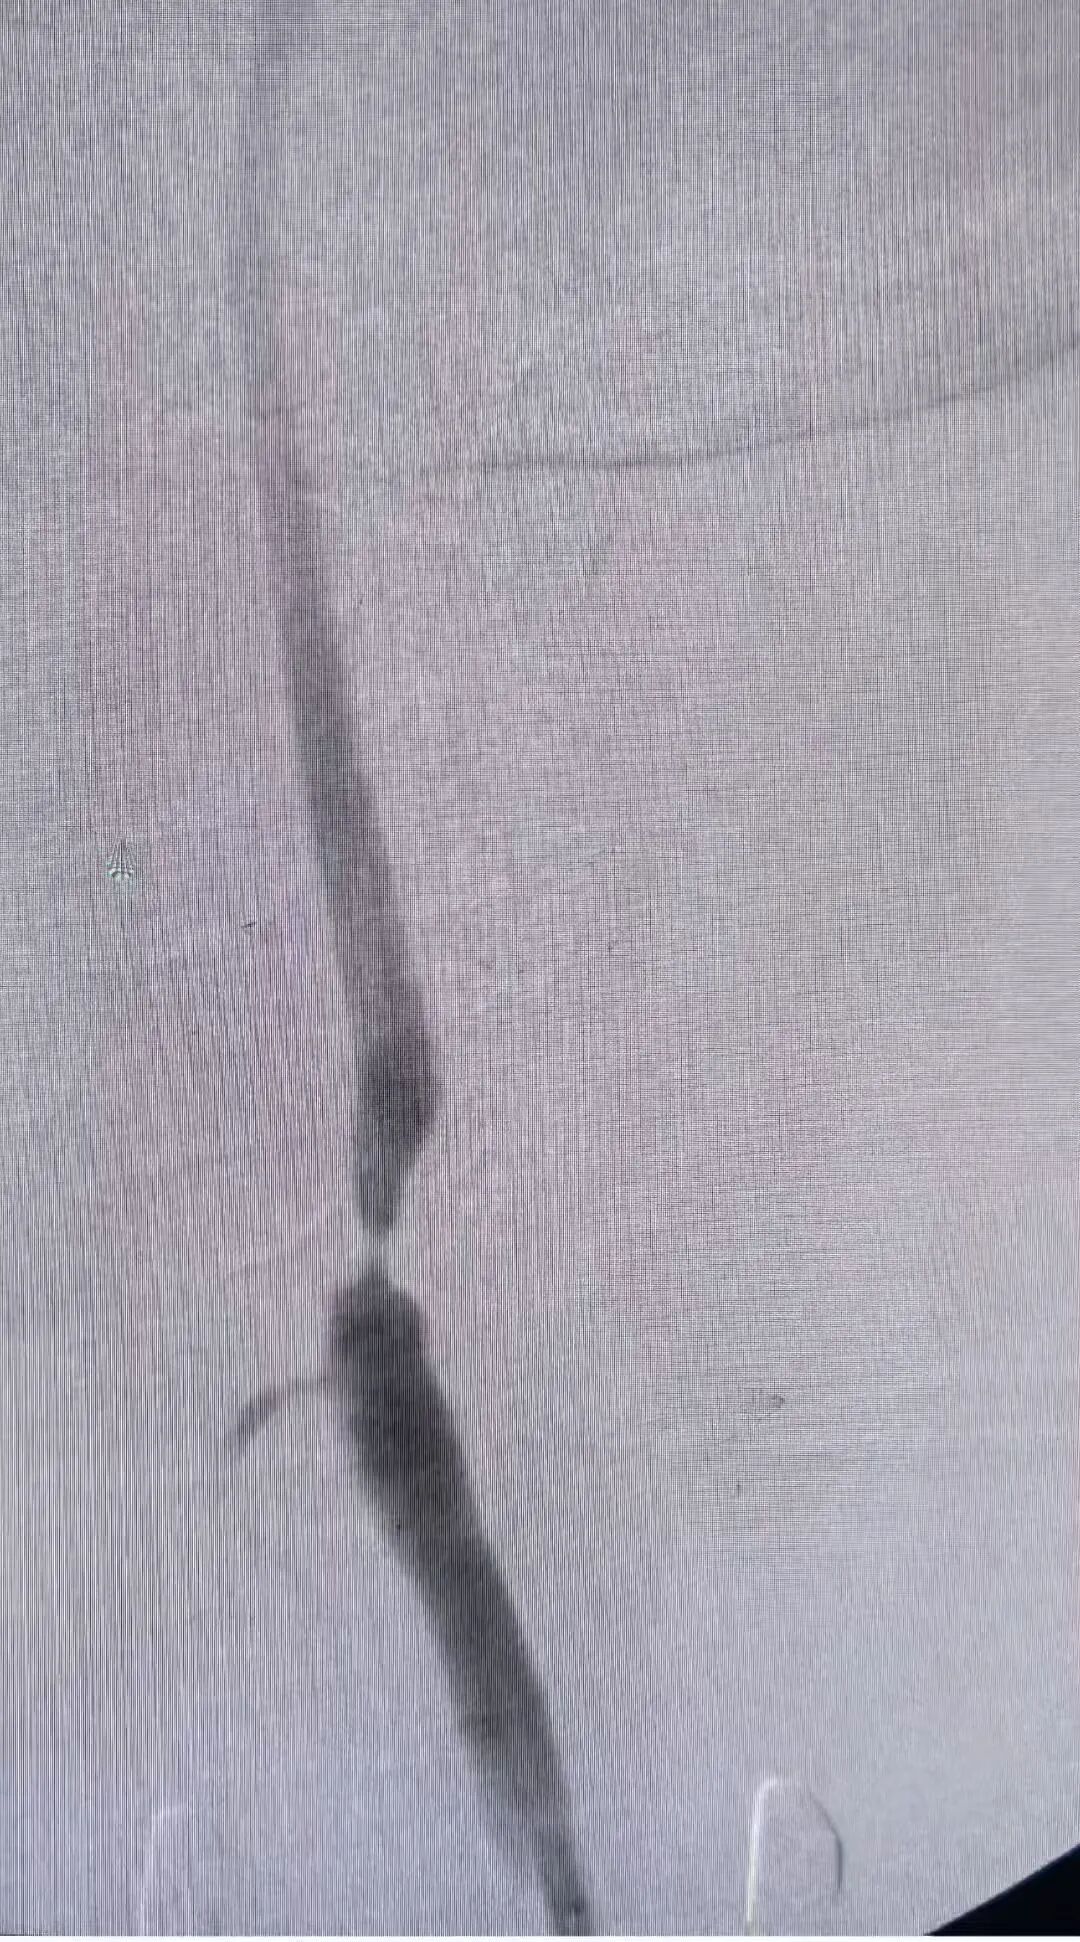

术前及术后造影图像: